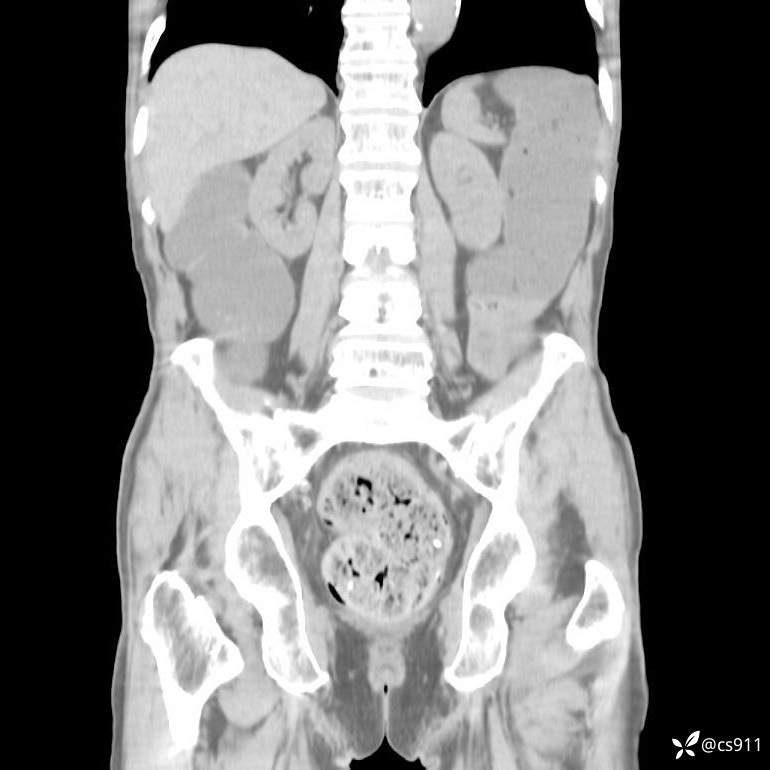

急腹症之急诊CT,原因?答案公布

男,77岁,腹痛、腹胀伴恶心呕吐1天。呕吐胃内容物,非喷射性呕吐,有咖啡色样胃内容物,诉有胃穿孔病史。查体:全腹平,下腹部压痛,全腹无反跳痛,叩诊呈浊音,移动性浊音阴性,肠鸣音减弱,1-2次/分。肛检:直肠未扪及明显肿物,可触及大量粪块。

血淀粉酶(AMY) HH 1859 U/L 35-135

癌胚抗原(CEA) H 27.44 ng/ml 0-5